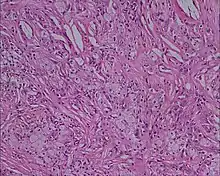

Xanthoma tuberosum

Xanthoma tuberosum (also known as tuberous xanthoma) is characterized by xanthomas located over the joints.[2]: 530